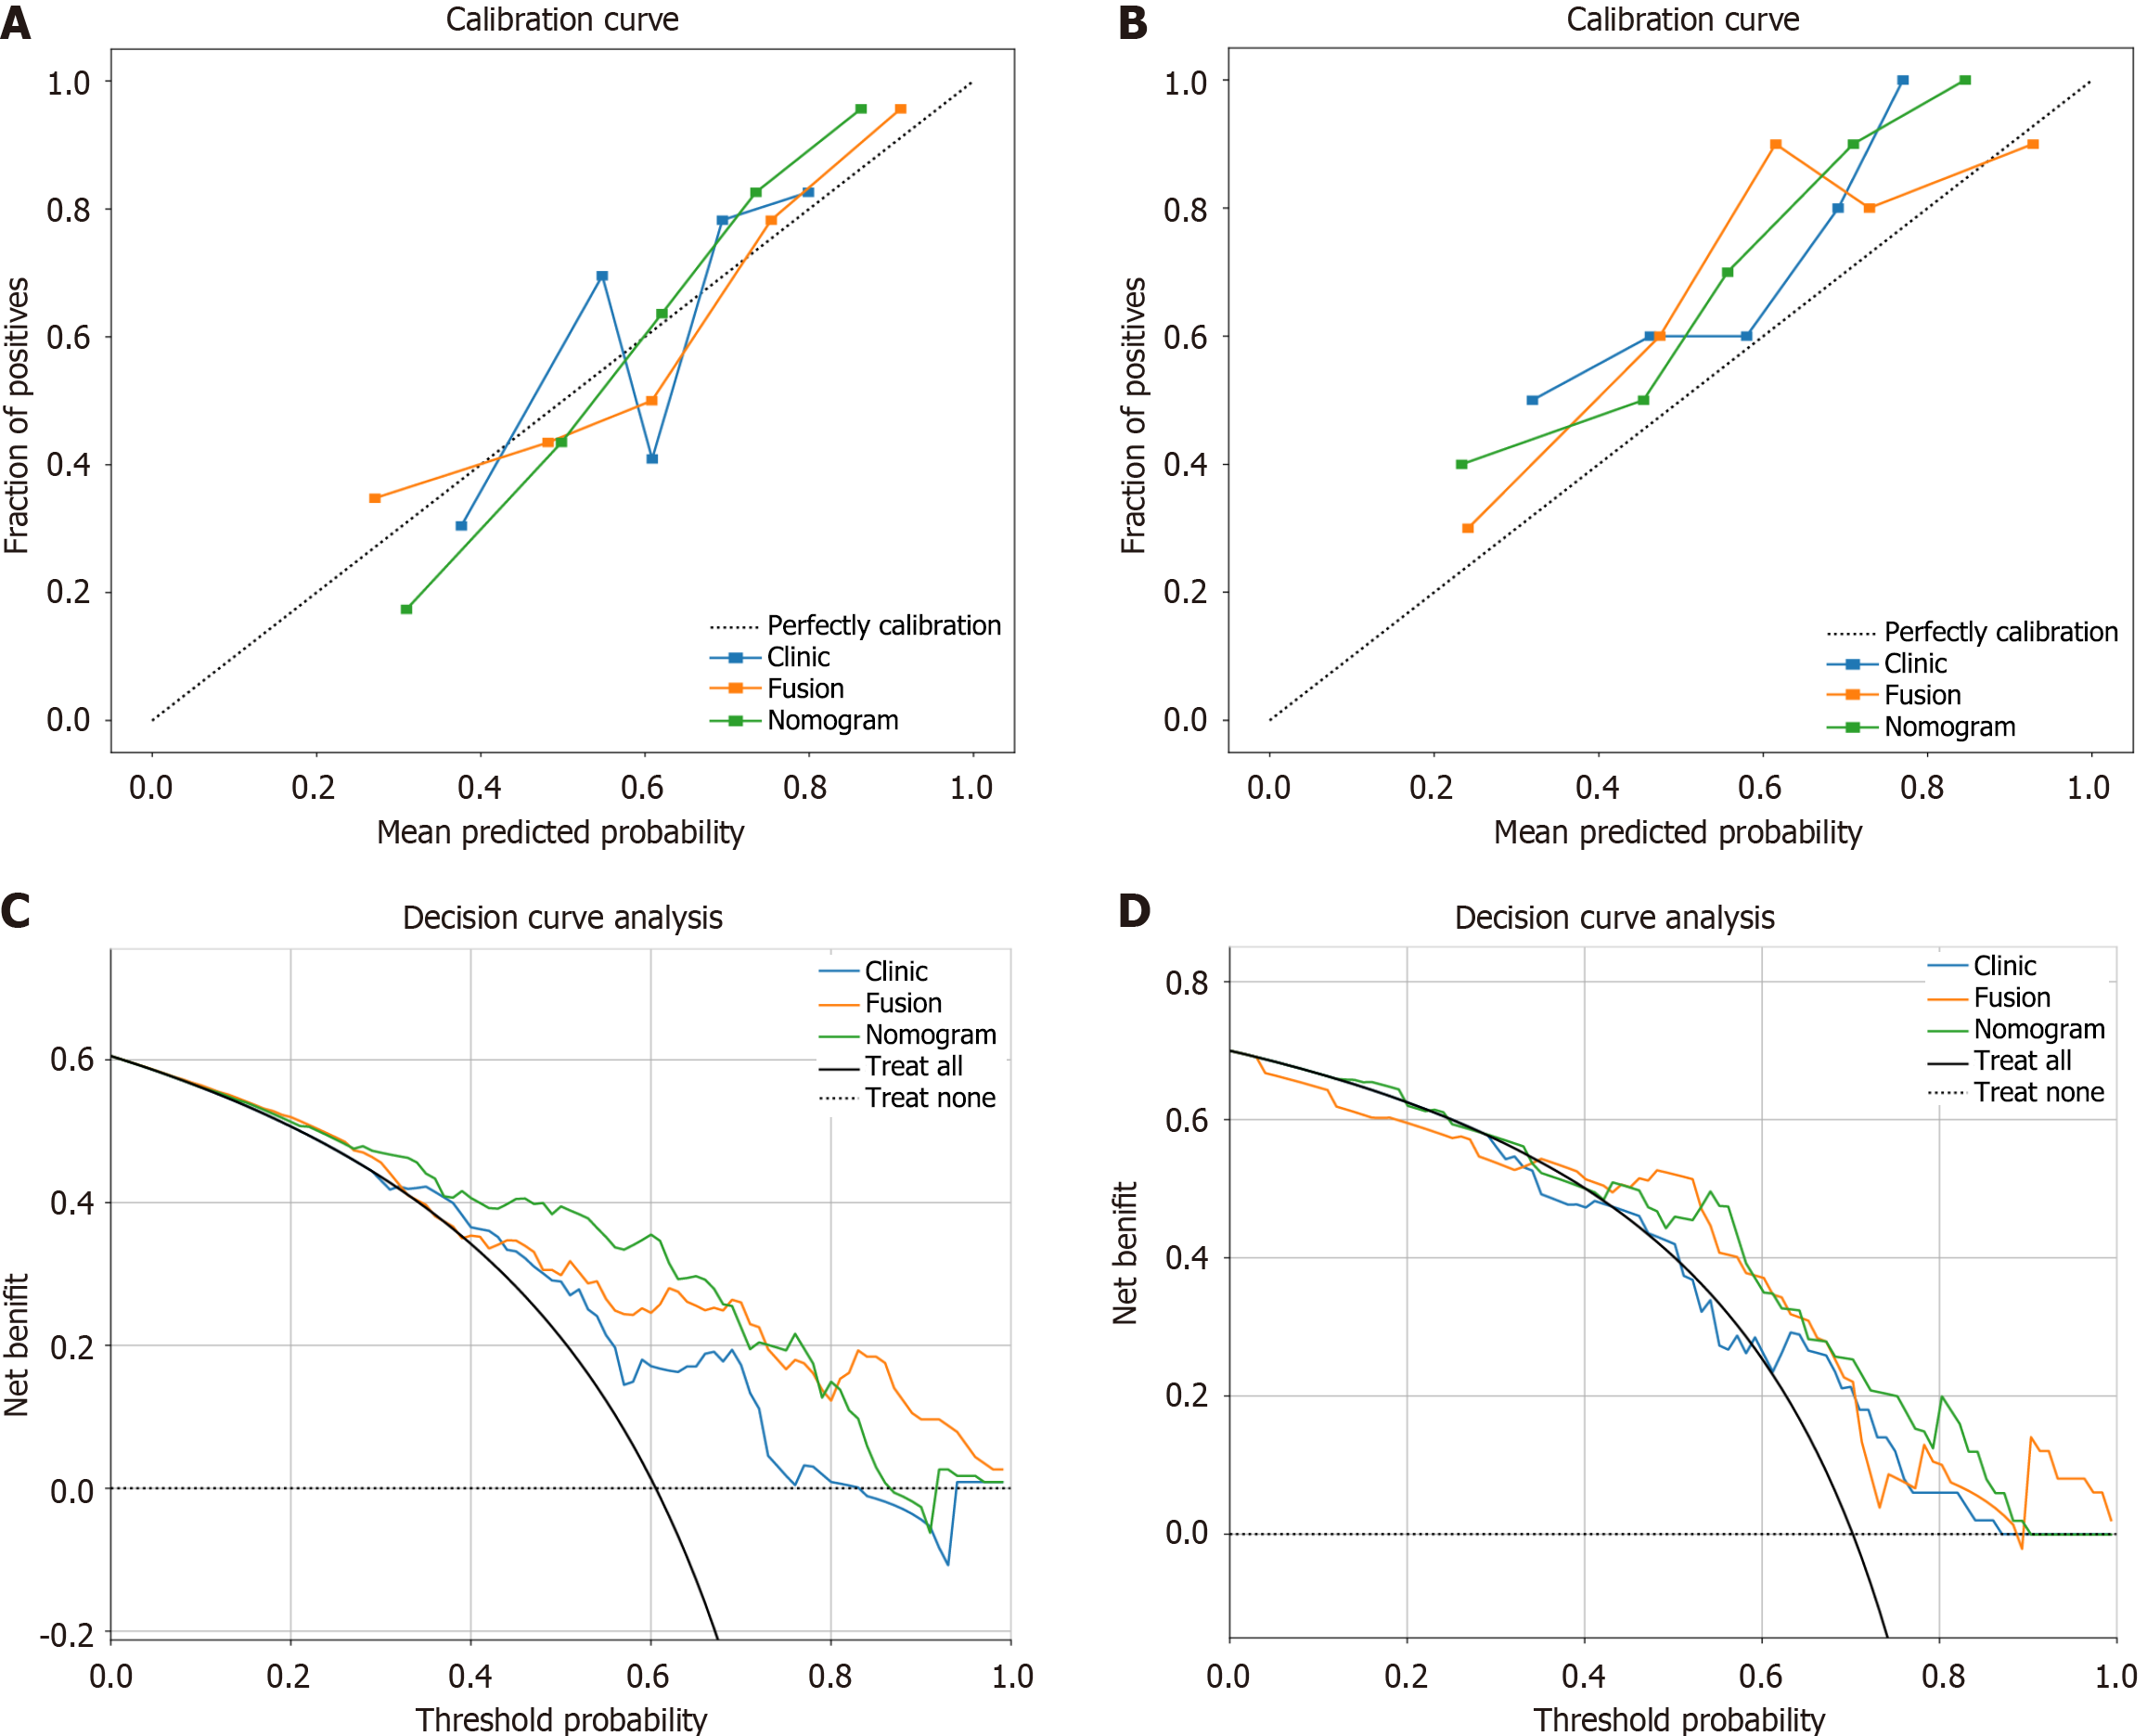

All the calibration curves diagrams and DCA for the training and validation groups of the three models are presented in Figure 8. The Hosmer-Lemeshow test revealed P values higher than 0.05 for all models (training group: P = 0.672, 0.570, and 0.339; validation group: P = 0.121, 0.202, and 0.109), suggesting good consistency between the predicted and actual Ki-67 expression. DCA demonstrated that the nomogram yielded a greater overall net benefit in assessing Ki-67 expression status than did the clinical model or the radiomic model alone.